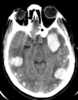

Multiple intracranial calcification